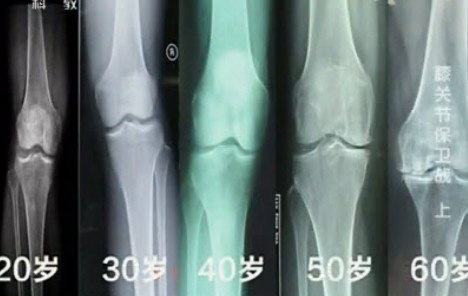

膝关节从什么年龄开始退化?30岁?40岁?50岁?

正确答案是膝关节从30岁开始退化。

专家观点:长期的负重运动可导致膝关节退变。